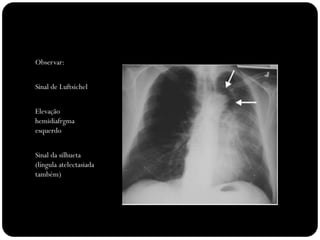

Observar:

Sinal de Luftsichel

Elevação

hemidiafrgma

esquerdo

Sinal da silhueta

(língula atelectasiada

também)

Atelectasia do lobo

inferior esquerdo

Atelectasias de lobos

inferiores deslocam

o hilo posterior e

medialmente;